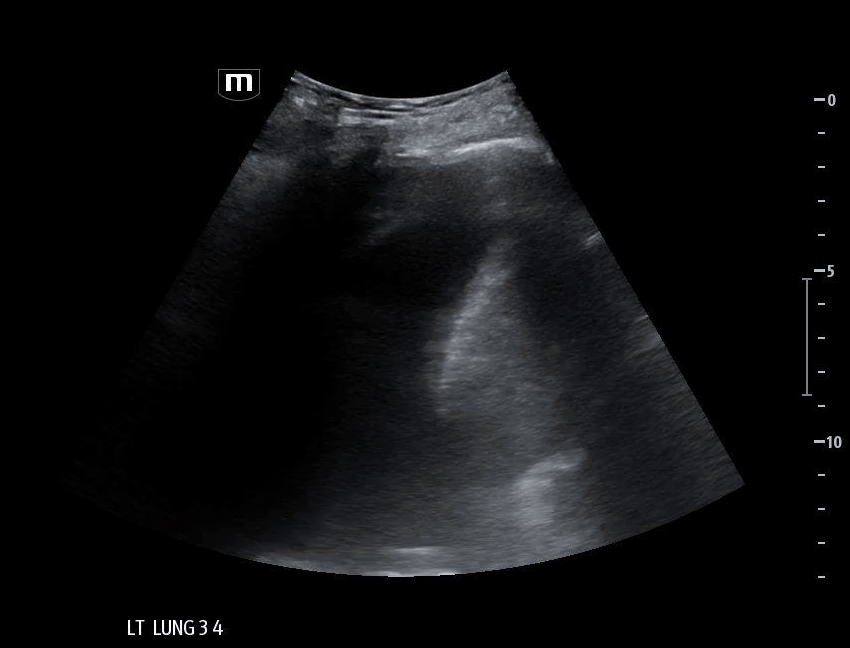

Left lung base

Patient’s CT chest came back positive for right sided aspiration pneumonia and right lung collapse secondary to pleural effusions.